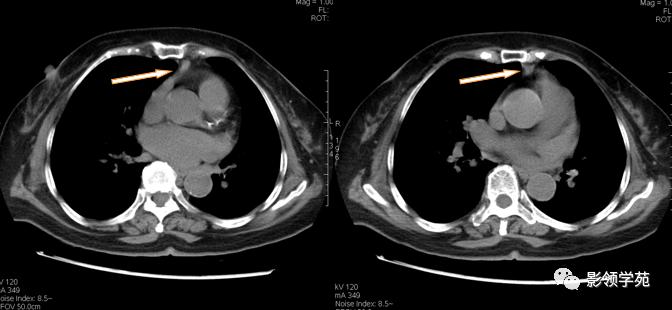

淋巴结肿大融合,压迫上腔静脉,致上腔静脉狭窄

淋巴结肿大融合,轻度强化,与血管形成鲜明对比